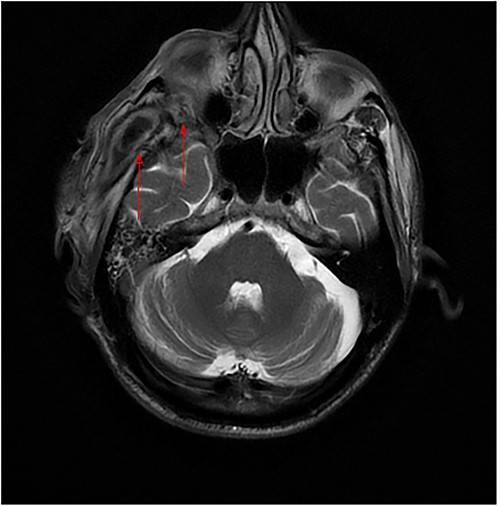

The patient’s head and neck were imaged using magnetic resonance imaging (MRI) and computed tomography scan, which revealed the presence of abscess collections in the submasseteric space, pterygomandibular space, deep temporal space and infratemporal abscess spreading to the orbital cavity through a bony defect in the lateral orbital wall, all of which were not addressed during the first procedure (Figs 2 and 3).

Axial MRI of the head, a dumbbell-shaped lesion (red arrows) representing an infratemporal abscess invading the orbital cavity through the bony erosion of the lateral orbital wall.

Most cases of odontogenic orbital complications arise from upper jaw tooth infections [4]. What is unique about our case is the unusual route by which the infection spread into the orbit. In our case, the hypothesized path of spread started from the lower third molar infection to both the submasseteric and pterygomandibular spaces and then passed into the infratemporal fossa, where a focus of abscess was loculated, making its way into the orbit through a bony defect in the lateral orbital wall, forming an interesting dumbbell-shape appearance on MRI (Fig. 2a).